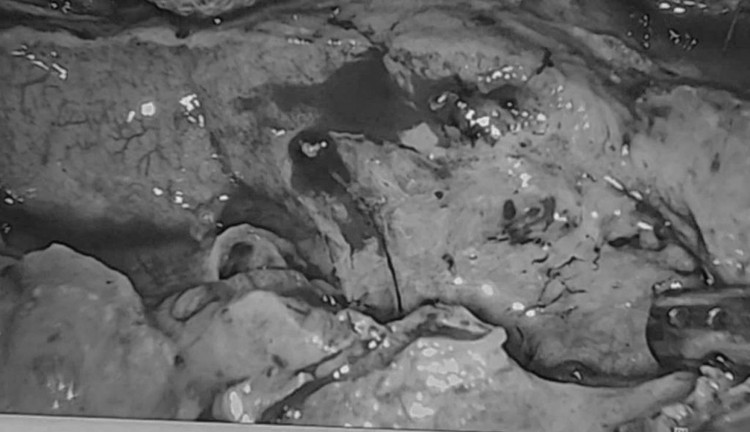

![]() |

| Hình ảnh phẫu thuật - Ảnh BVCC |